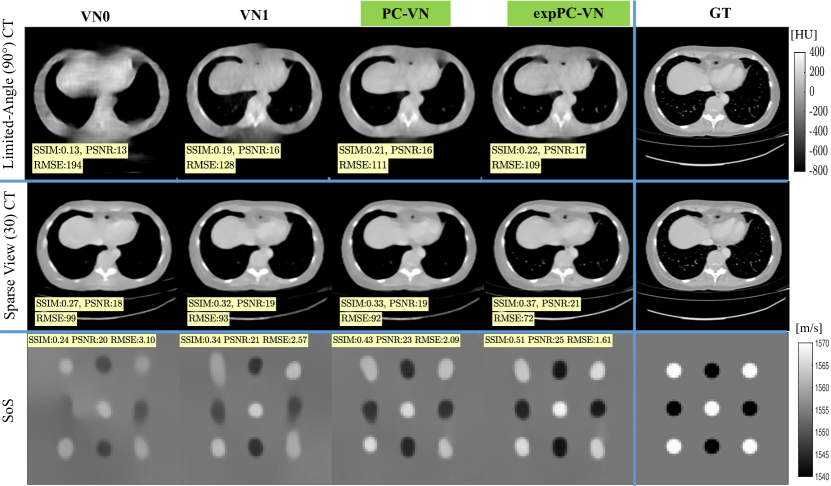

Evaluation. For quantitative comparison of reconstruction and ground truth, we calculated structural similarity index measurement (SSIM) [16], Root Mean Square Error (RMSE), and peak signal-to-noise ratio (PSNR) as follows:

where is the dynamic range of the ground truth image. The corresponding values are reported in Hounsfield units (HU) and m/s, for X-ray CT and USCT SoS experiments accordingly. We denote the architectures employed in [3] and [15] as VN0 and VN1, respectively. As seen in Fig. 2 the proposed preconditioned network (PC-VN) with sinogram convolutions improves reconstruction accuracy and quality for all X-ray CT acquisition scenarios and USCT as suggested by RMSE and SSIM values. As reported in Tab. 1, training the proposed network using exponentially weighted loss (expPC-VN) defined in Eq. (3) further improves reconstruction quality and reduces the variance of error, which can be explained by the introduced regularization effect. Fig. 3 shows that expPC-VN outperforms iterative methods both in terms of accuracy and image quality. Namely, compared to nonlinear reconstruction methods, we observe improvements of RMSE by 49% in the CT-LA-60∘ scenario, and increase of SSIM by 38% in the CT-SV-15 experiment. Quantitative results from Tab. 1 and Fig. 3 show that proposed reconstruction method outperforms all considered iterative and deep learning -based approaches.